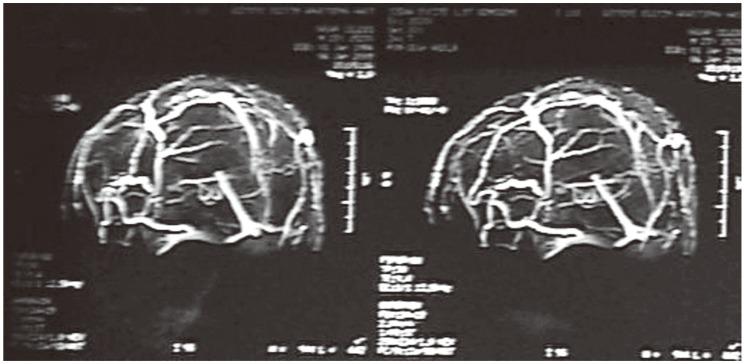

Pseudotumor cerebri is a condition of increased intracranial pressure in the absence of clinical, laboratory or radiological pathology. Spinal intradural hematoma formation after lumboperitoneal shunt (LPS) implantation is very rare, but it can cause sudden and serious deterioration. In this report, we present a patient who developed an intradural hematoma following LPS operation. A 27-year-old male patient suffering from headaches and progressive vision loss was diagnosed with pseudotumor cerebri. He underwent LPS operation in January 2009. Four hours after the operation, he developed urinary and fecal incontinence with paraparesis (1/5). Lumbar magnetic resonance imaging identified an intradural hematoma at the level of L2-L3, and he was reoperated. The intradural hematoma was removed. Physical therapy was started because of paraparesis. Two months later, the patient's muscle strength had increased to 3/5. Surgeons must remember that, LPS implantation can cause a spinal intradural hematoma in a small percentage of patients, with catastrophic results.